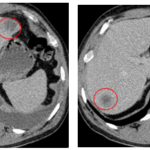

CASE LÂM SÀNG: CHẨN ĐOÁN BỆNH NHÂN MẮC HAI UNG THƯ: GIST RUỘT NON VÀ UNG THƯ TUYẾN GIÁP TẠI TRUNG TÂM Y HỌC HẠT NHÂN VÀ UNG BƯỚU, BỆNH VIỆN BẠCH MAI

Ca lâm sàng